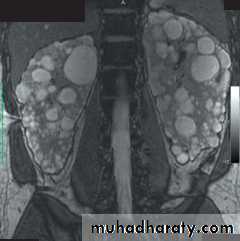

MRI images of the kidneys. A Normal kidneys. B Polycystic kidneys; although the kidney enlargement is extreme.

A

B